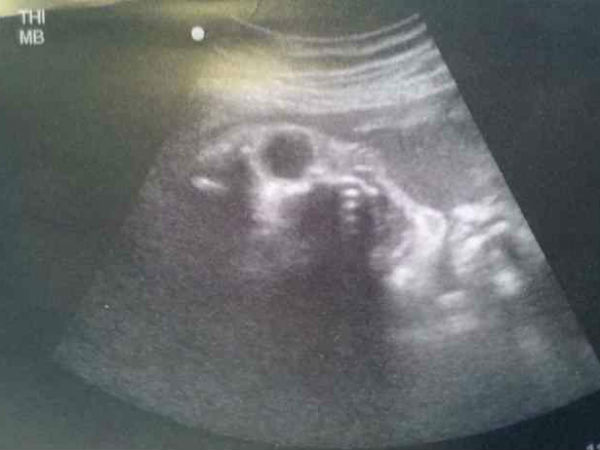

ಚಿತ್ರ#1 ಅನ್ಯಗ್ರಹದ ಮಗುವೇ ಇದು?

ಈ ಚಿತ್ರದಲ್ಲಿ ಕಾಣುವ ಮಗುವಿನ ಚಿತ್ರ ಯಥಾವತ್ತಾಗಿ ಒಂದು ಅನ್ಯಗ್ರಹ ಜೀವಿಯ ಮುಖದಂತೆ ಕಾಣುತ್ತಿದೆ ಅಲ್ಲವೇ? ಇದು ಎಷ್ಟು ನಿಜವಾಗುತ್ತದೆ ಎಂಬುದನ್ನು ಹೆರಿಗೆಯ ಬಳಿಕವೇ ಖಚಿತಪಡಿಸಬೇಕಷ್ಟೇ. ಈ ಮಗು ಎಲ್ಲರಂತೆ ಮುದ್ದು ಮುಖವನ್ನೇ ಹೊಂದಿರಲಿ ಎಂದು ನಾವೆಲ್ಲಾ ಹಾರೈಸೋಣ. ಈ ಚಿತ್ರವನ್ನು ಯಾವಾಗ ಮಹಿಳೆಯ ಸದಸ್ಯರೊಬ್ಬರು ತೆಗೆದು ಸಾಮಾಜಿಕ ತಾಣದಲ್ಲಿ ಪ್ರಕಟಿಸಿದರೋ, ಆಗಿನಿಂದ ಲಕ್ಷಾಂತರ ಮೊಬೈಲುಗಳಲ್ಲಿ ಇದು ಹರಿದಾಡುತ್ತಿದೆ.